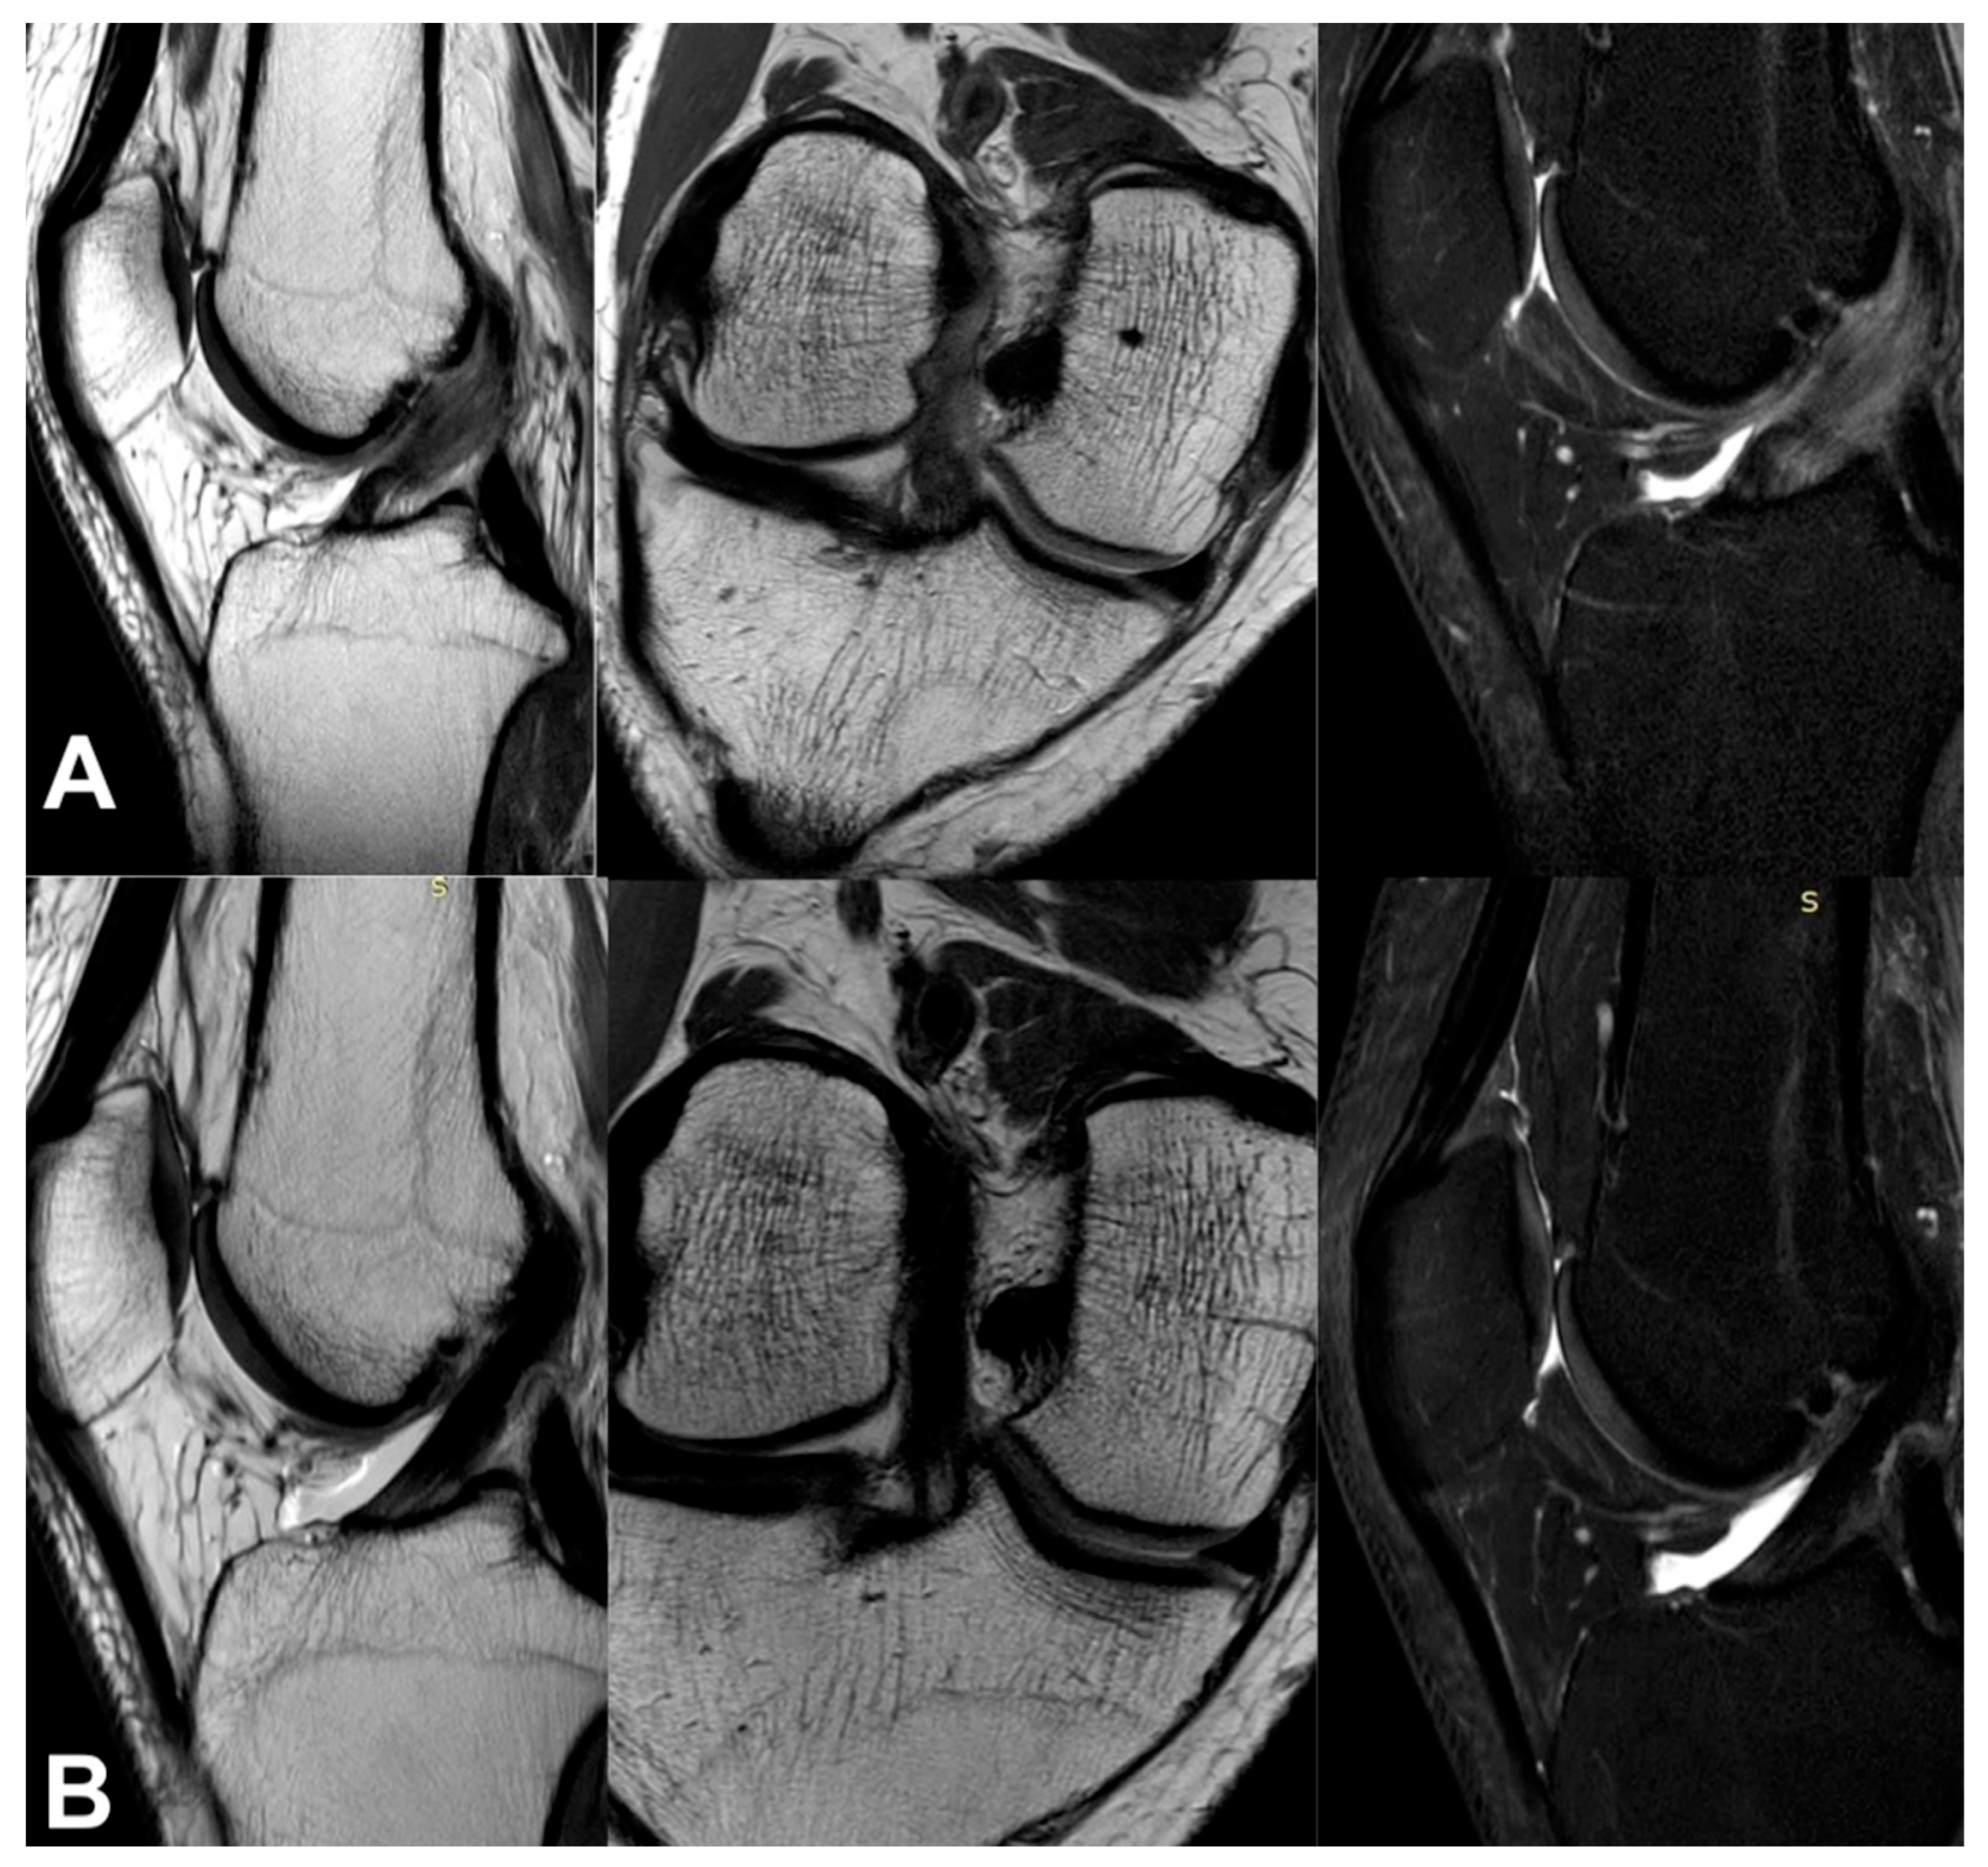

Figure 6.

The same knee MRI scans of a patient with an anterior cruciate ligament tear before treatment (A) and corresponding MRI scans after nanosurgery treatment with an RP-hCM injection (B).